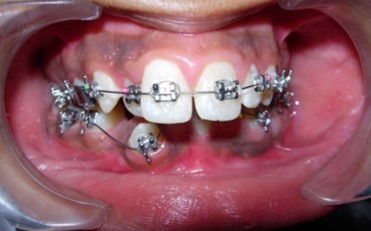

Initial alignment was done with upper and lower 0.014-inch nickel titanium archwires (Figure 6a,Figure 6b,Figure 6c). This was followed with 0.016-inch nickel titanium archwires. Space for blocked out 42 was created by an open coil spring on a 0.018-inch stainless steel archwire. Deep bite was corrected with a lower 0.016-inch reverse curve nickel titanium wire. Extraction spaces in the maxillary and mandibular dental arches were closed with 9mm nickel titanium retraction coil springs attached to crimpable hooks on 0.017 x 0.025-inch stainless steel archwires and finishing and detailing was completed with 0.019 x 0.025-inch stainless steel archwires.

Figure 6a.Initial levelling and alignment – Upper / Lower 0.014-inch nickel titanium wires – Frontal

Initial levelling and alignment – Upper / Lower 0.014-inch nickel titanium wires – Frontal

Figure 6b.Initial levelling and alignment – Upper / Lower 0.014-inch nickel titanium wires – Right

Initial levelling and alignment – Upper / Lower 0.014-inch nickel titanium wires – Right

Figure 6c.Initial levelling and alignment – Upper / Lower 0.014-inch nickel titanium wires – Left

Initial levelling and alignment – Upper / Lower 0.014-inch nickel titanium wires – Left